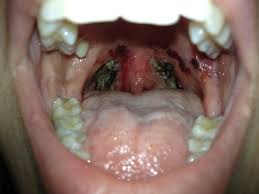

Resultado de imagem para dor de garganta inflamada